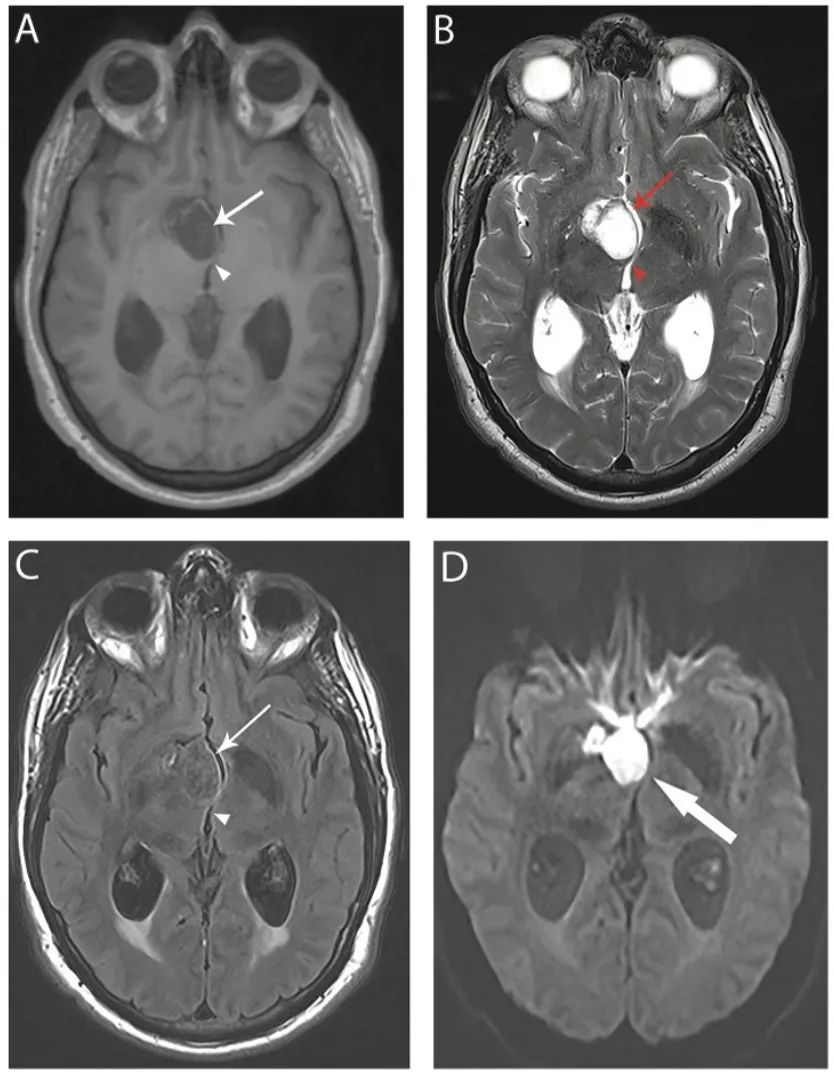

图19 表皮样囊肿

轴位T1 (A)、T2 (B)和FLAIR(C)像显示鞍上区有一个突出的囊肿(箭头),为T1低信号、T2高信号、FLAIR等信号,囊肿引起丘脑的占位效应,引起第三脑室变形(箭头)。DWI像(D)显示囊肿明显高信号(箭头),不同于蛛网膜囊肿。